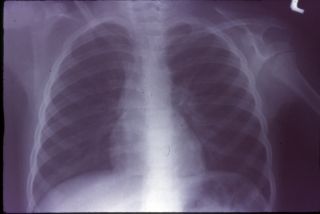

جسم خارجی Foreign Bodies